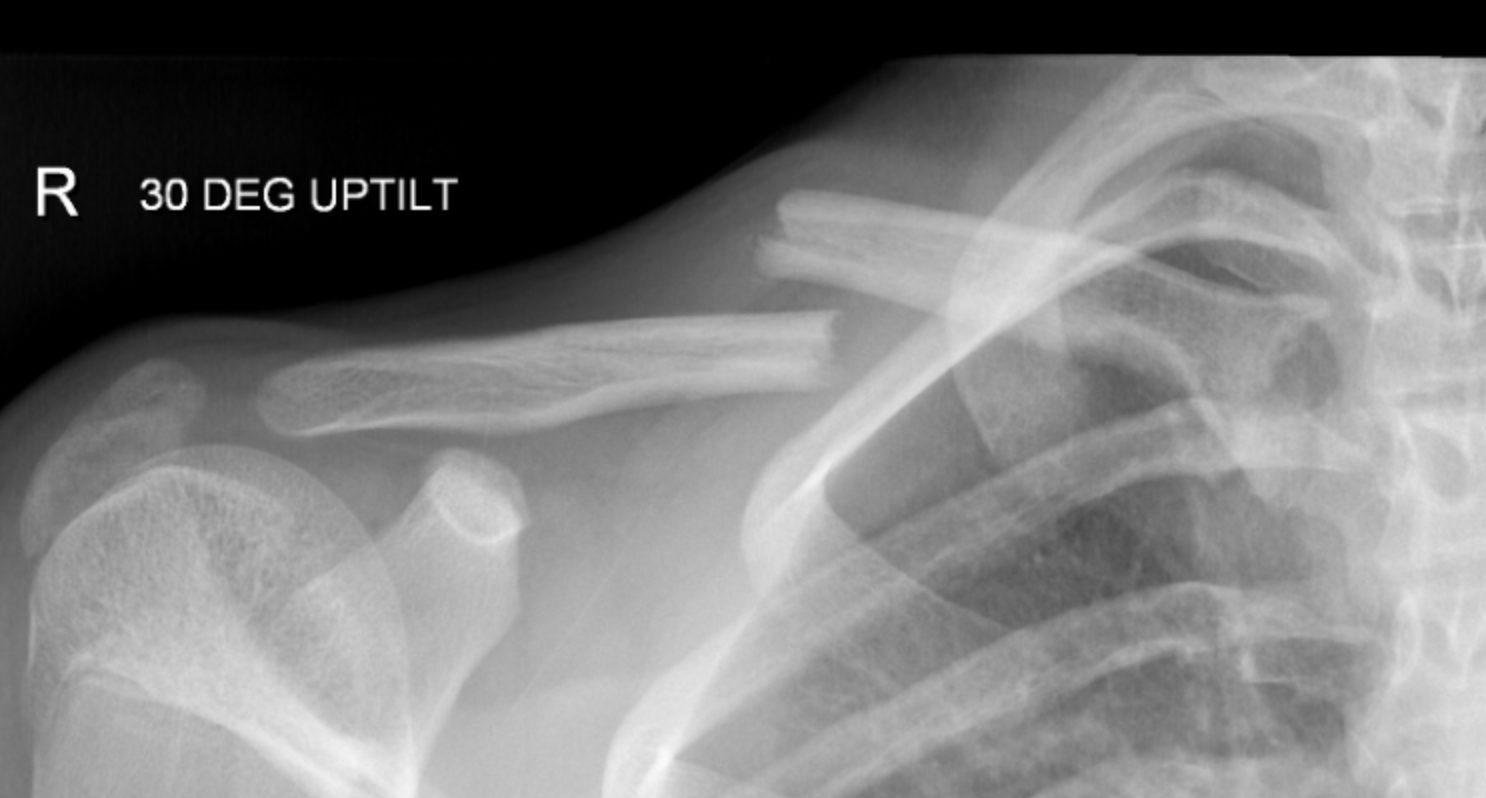

Your clavicle is: A bone that lies horizontally and connects the shoulder and arm to the sternum (breastbone).

Dr. Ahmad and his team of health professionals will greet you and start your visit with a discussion of your symptoms, sport, level of competition, or desired activity level, and how the injury occurred. Next, the doctor will exam your clavicle injury, focusing on:

- X-ray results to determine the features of the fracture

Dr. Ahmad will recommend non-surgical treatment if your bones are still in proper position, and have not shifted to the point where readjustment is necessary. Nonsurgical treatment may include:

Dr. Ahmad and his team will recommend surgery if the broken ends of the bones have significantly shifted out of place, especially in high demand athletic patients. Surgery involves re-positioning the broken bone pieces and preventing them from moving.